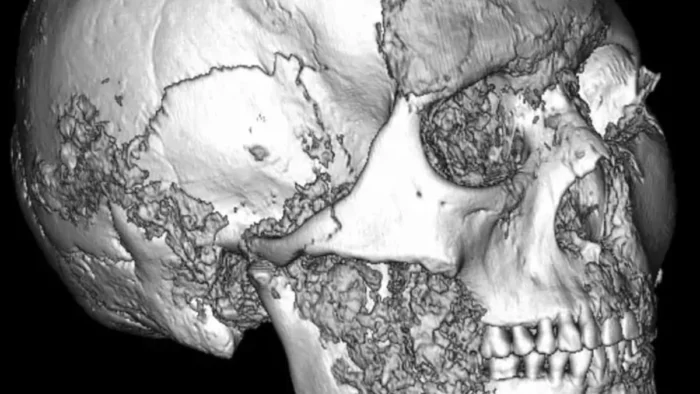

Esa necesidad de abrir la boca, fijar el hueso y devolver movilidad a la mandíbula es justo lo que un equipo de investigadores rusos ha documentado al revisar los restos de una mujer Pazyryk hallada en 1994. El grupo detectó con tomografía computarizada una operación compleja en la articulación temporomandibular derecha que permitió a la paciente sobrevivir tras una lesión grave.

El hallazgo sitúa esa intervención hace unos 2.500 años y la convierte en uno de los casos más antiguos conocidos de cirugía mandibular de este tipo. La revisión se centró en el cráneo conservado en el permafrost de la meseta de Ukok, en el sur de Siberia.

Las imágenes médicas revelaron que el impacto había aplastado el hueso temporal y destrozado la articulación que conecta la mandíbula con el cráneo, situada junto al oído. La mandíbula había quedado fuera de su eje, una situación que habría impedido hablar con claridad y comer por el lado derecho.

La tomografía también permitió identificar dos conductos estrechos de unos 1,5 milímetros perforados en ángulo recto en los huesos que forman la articulación dañada. En el interior aparecieron restos de un material flexible, probablemente crines de caballo o tendón animal, que habría servido para mantener unidas las superficies articulares.